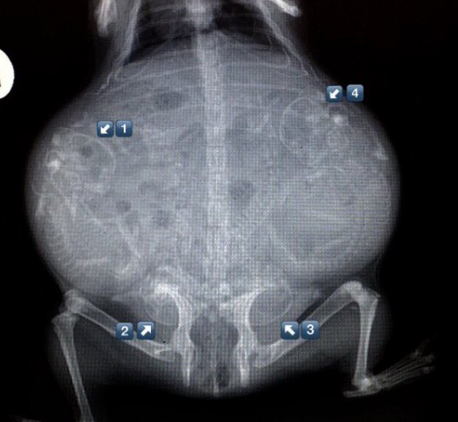

▼怀孕的狗狗